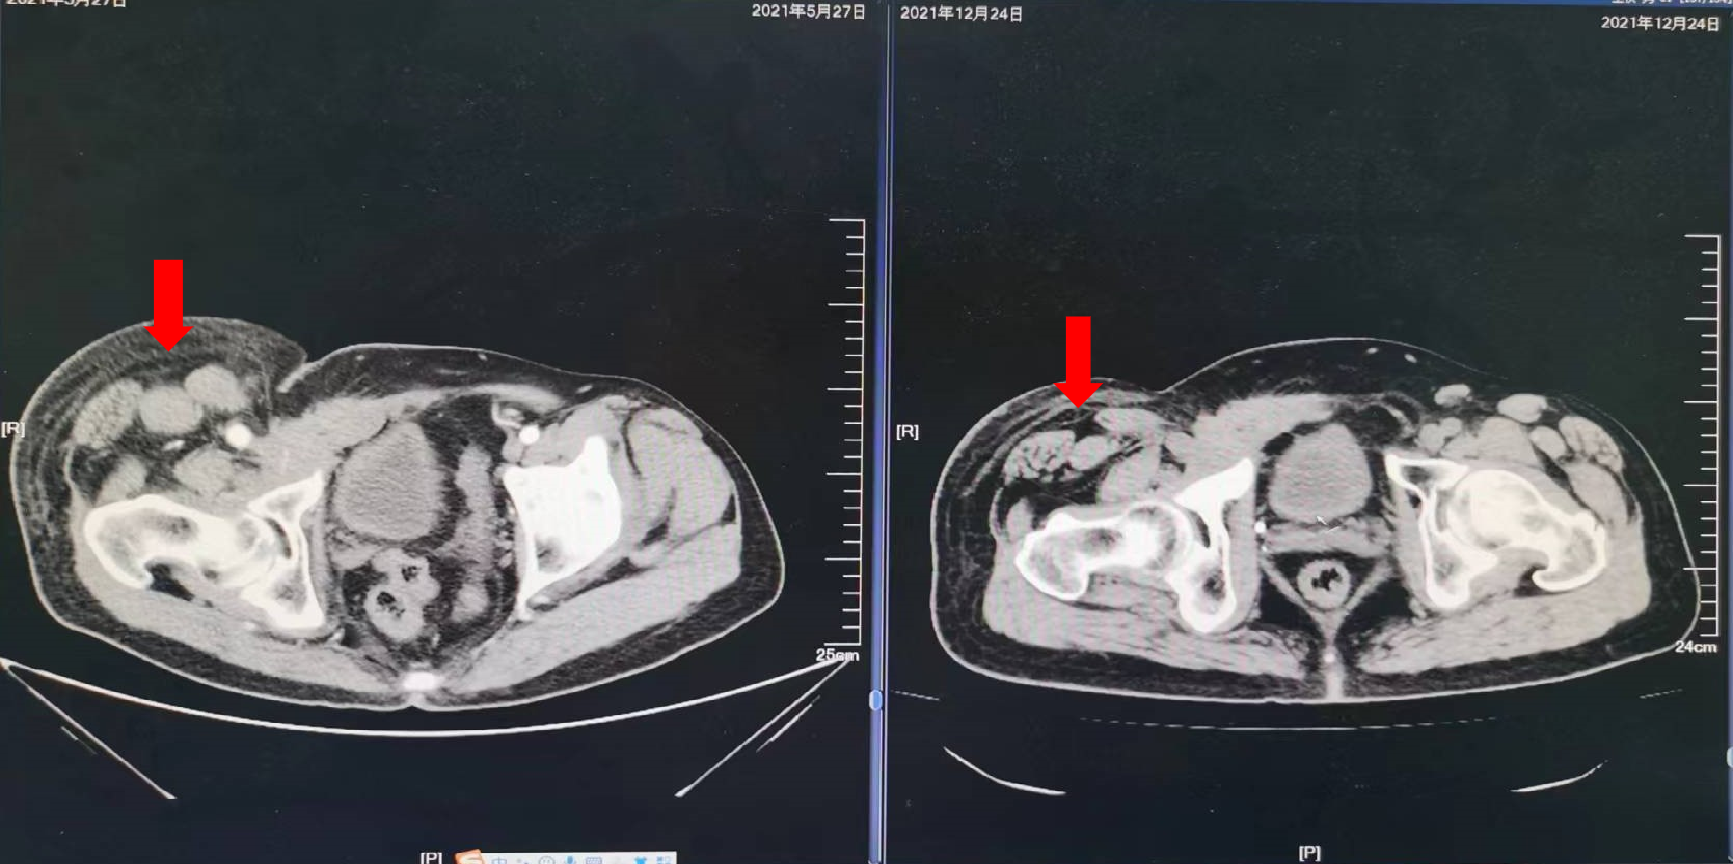

2021年5月27日:开始口服曲氟尿苷替匹嘧啶片(TAS-102)55mg每日2次 d1-5,d8-12,Q4W配合信迪利单抗免疫治疗。

疗效评价:SD,患者右腹股沟肿胀疼痛明显减轻,停用止痛药,PFS时间为10个月,主要不良反应为Ⅱ度骨髓抑制。